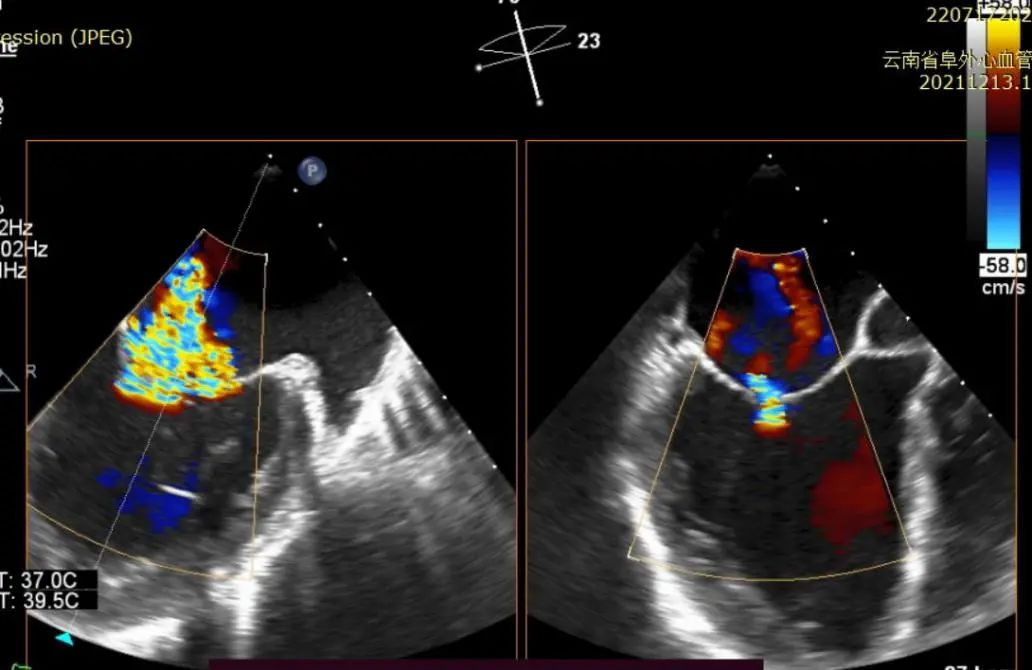

投射下提示瓣膜夹植入及锁定完成(图3)

手术采用经典股静脉-房间隔入路,房间隔穿刺后将瓣膜夹输送系统送入左心房,在TEE引导下捕捉二尖瓣前后瓣叶,并关闭瓣膜夹。经TEE反复确认手术效果后最终释放瓣膜夹。术中仅植入一枚JensClip瓣膜夹就达到了良好的治疗效果,术后即刻心超二尖瓣反流减少到0-1+,瓣膜夹位置稳定,功能良好。术后患者症状明显好转,术后复查TTE反流0-1+,瓣膜夹位置稳定,拟于近期出院。